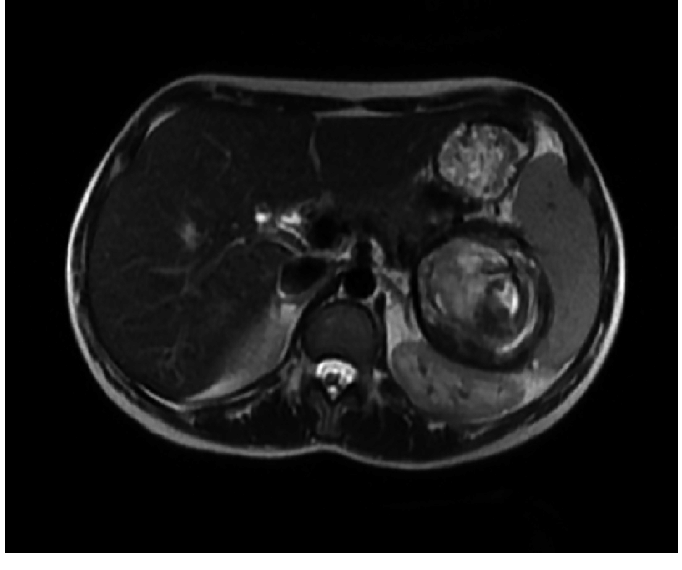

В режиме Т1 определяется гипоинтенсивный сигнал от просвета сосуда, при этом в стенке аневризмы или в пристеночном тромбе может наблюдаться неравномерный сигнал в зависимости от стадии организации.

В режиме Т2 визуализируется гиперинтенсивный сигнал от тромботизированного сегмента и окружающей ткани при воспалительных изменениях или паравазальном фиброзе.

В режиме с контрастированием фиксируется чёткое накопление контраста в аневризматическом мешке с возможной визуализацией дефекта наполнения при наличии тромба.

В артериальной фазе контрастирования визуализируется интенсивное накопление контраста в аневризматическом мешке с возможным дефектом наполнения, соответствующим пристеночному тромбу.

Гипоинтенсивный сигнал в Т1 и Т2, возможно отсутствие контрастирования в зоне тромба |

Дефект контрастного наполнения с плотностью, отличной от кровотока, особенно на артериальной фазе |